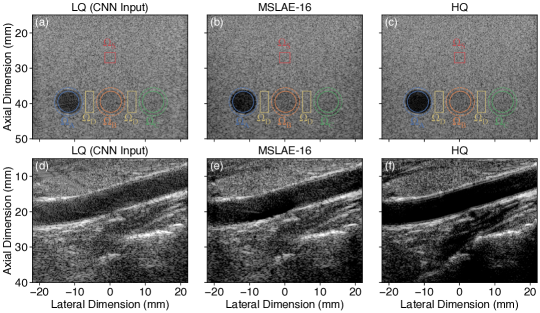

Fig. 6 shows the experimental results of an example image for both in vitro (top row) and in vivo (bottom row) acquisitions. Overall, it can be observed that, despite using only simulated data for training, the key effects of the proposed approach translated well to experimental settings.

Refer to caption\phantomsubcaption\phantomsubcaption\phantomsubcaption\phantomsubcaption\phantomsubcaption\phantomsubcaption

Fig. 6: B-mode image representations of an in vitro test phantom (top row, 787878-dB/dividedecibelabsent\mathrm{dB}\text{/} range) and an in vivo carotid sample (bottom row, 505050-dB/dividedecibelabsent\mathrm{dB}\text{/} range): 6 and 6 single \glsxtrfullpw \glsxtrfulllq images; 6 and 6 images recovered from \glsxtrshortlq using the proposed \glsxtrfullcnn-based image reconstruction method with the selected trained \glsxtrshortcnn (i.e., \glsxtrshortmslae-161616); 6 and 6 reference \glsxtrfullhq images reconstructed from the complete set of \glsxtrfullsa acquisitions.

The visual assessment of in vitro results shows that both SL and GL artifacts (clearly visible in the anechoic inclusion) were strongly reduced. (Note that EW artifacts are harder to identify as they result in patterns that resemble speckle.) This effect was confirmed quantitatively by the contrast measured in each inclusion of the in vitro phantom (Table 3). The contrast in the anechoic inclusion was largely improved compared with LQ. However, the proposed approach seemed to slightly “overshoot” in the other two inclusions compared with HQ (reference). Speckle patterns were generally well-preserved. Yet, almost no improvement in the lateral resolution of speckle patterns was observed and measured (Table 3).

The in vivo experiments cover the full complexity of US imaging, namely highly diverse scattering processes, a wide range of echogenicities, and all physical effects neglected in the simulated dataset used for training. Yet, diffraction artifacts were strongly reduced, especially visible in zones where SL and GL artifacts aggregate [e.g., top left of Fig. 6]. Structures initially shadowed by such artifacts were well restored, up to some degree of residual artifacts. Image quality improvements were less visible in deeper regions, partially due to the fact that diffraction artifacts do not seem to be dominant there. Very fine and low-echogenic details, such as the carotid intima, were not accurately restored. An overall remaining clutter noise was observed, for instance within the carotid or in the anechoic regions below it (also in the LQ case). We computed standard image quality metrics, namely the PSNR, the SSIM, and the contrast between the tissue and the lumen. However, both the PSNR and the SSIM are strongly image-dependent and therefore not suitable for comparing different experiments. Also, contrast measures between ROIs in the tissue and in the lumen vary greatly depending on the choice of these ROIs and the level of artifacts contained within. We therefore chose not to report them and limited ourselves to a qualitative analysis. The complete in vivo sequence is presented in video format (Supplementary Material).